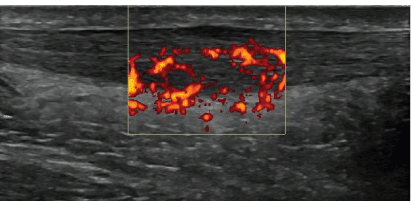

Longitudinal

Figure 1: Longitudinal ultrasound view of Achilles tendinopathy. Gray-scale and power-doppler ultrasound showing the sonographic findings characteristic of Achilles tendinopathy. The sonogram reveals the hypoechoic, darken area of the Achilles tendon, tendon thickening and neovascularization.